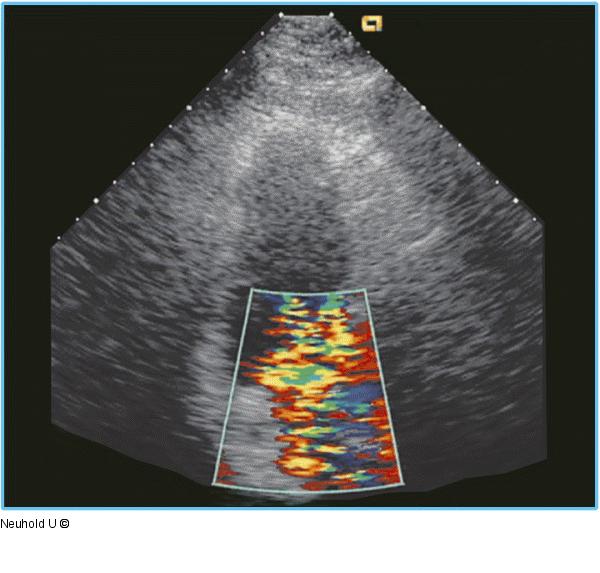

Abbildung 7: Dreikammerblick Dreikammerblick mti jetzt eindrucksvollem kräftigem exzentrischem MI-Jet. |

Dreikammerblick mti jetzt eindrucksvollem kräftigem exzentrischem MI-Jet. |